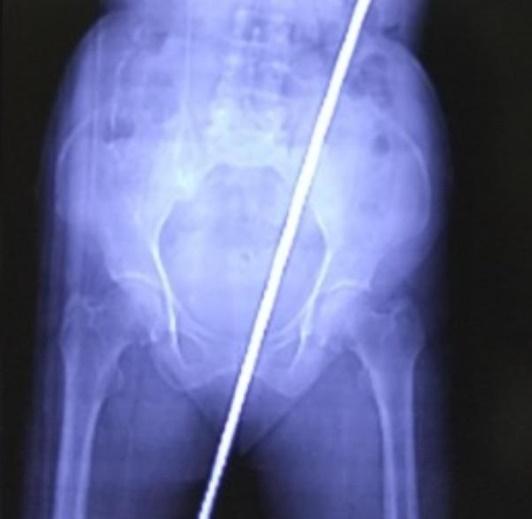

婦人被送到當地的卡斯圖爾巴醫學院搶救,透過X光和電腦斷層(CT)等檢查發現她被一支長達60厘米的生鏽鐵棍刺穿臀部,直插體內,她的肛管(anal canal)、直腸都被刺破,她的糞便亦流入體內,慶幸輸尿管、主動脈以及腎臟等重要部位都沒有受傷。醫生立即為她進行手術,順利將鐵棍移除,注射破傷風針與抗生素以避免感染後。手術後,婦人除了初期的噁心、腹痛、無法行走外,已經逐漸恢復,最後留院10天已可回家休養。